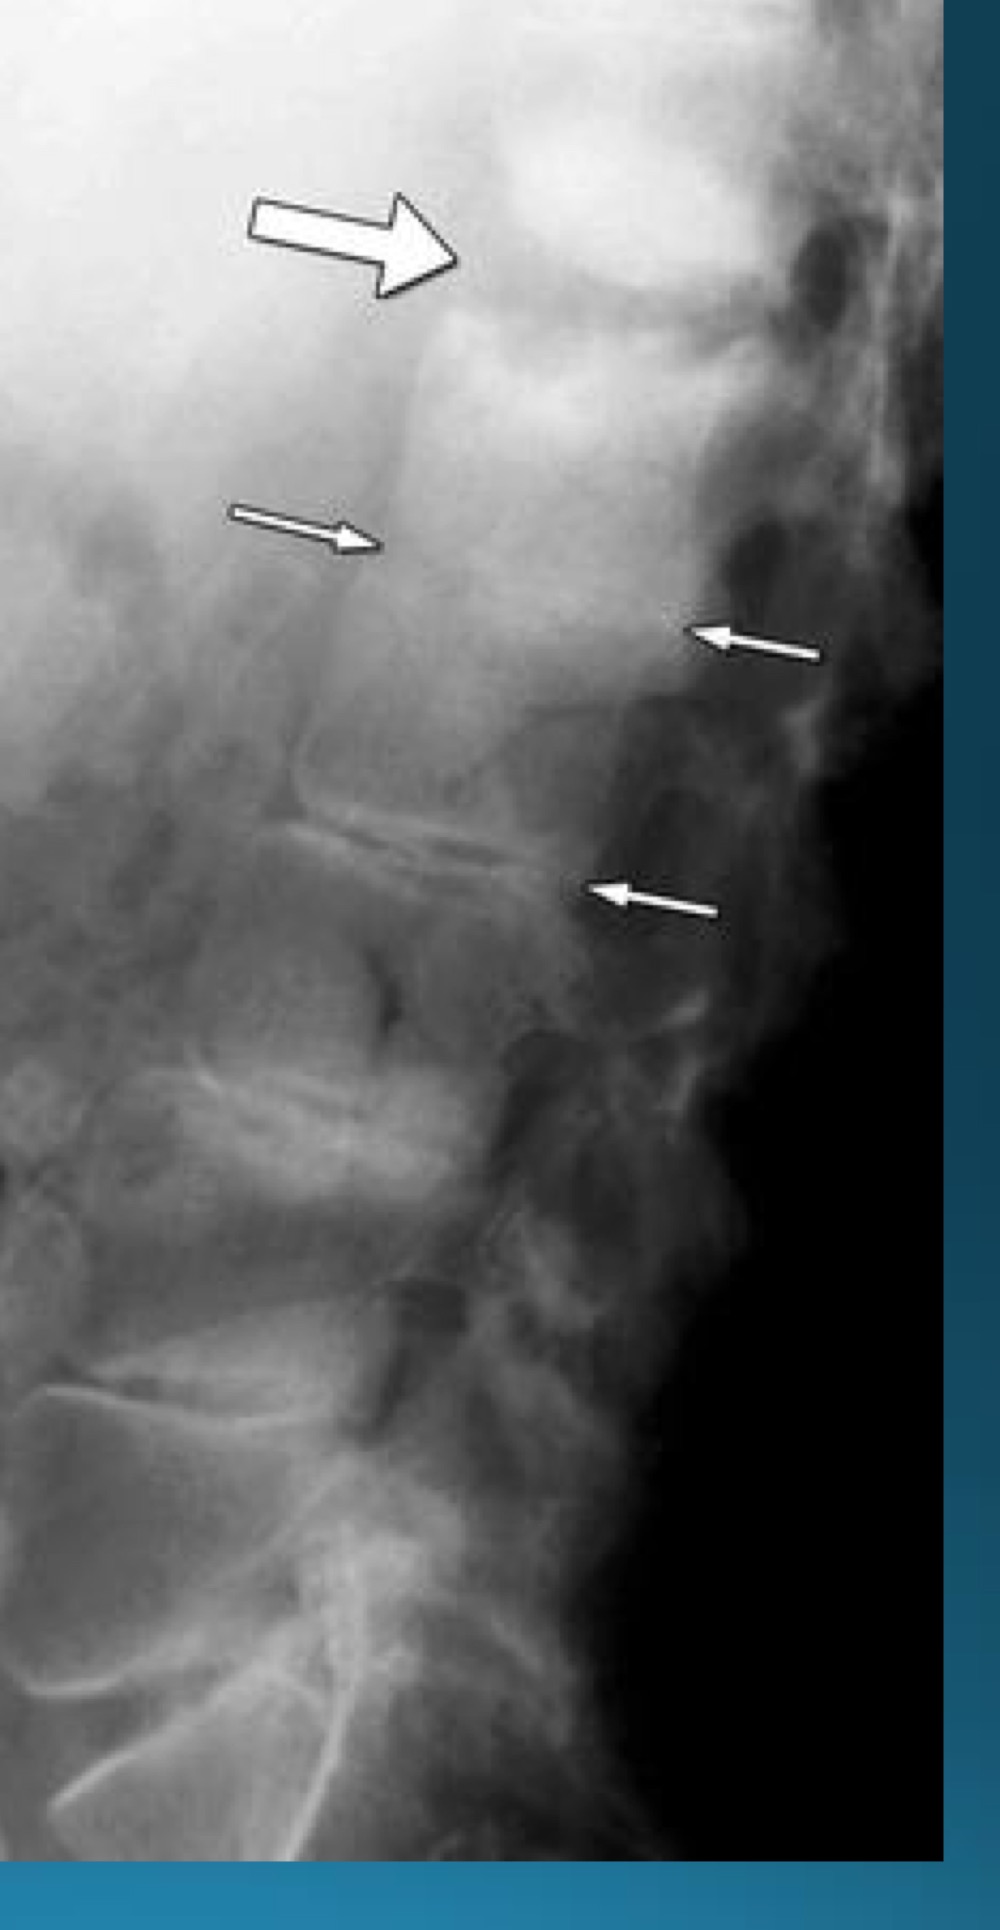

what do you call this sign? what diangosis is this apart of?

andersson lesion

AS